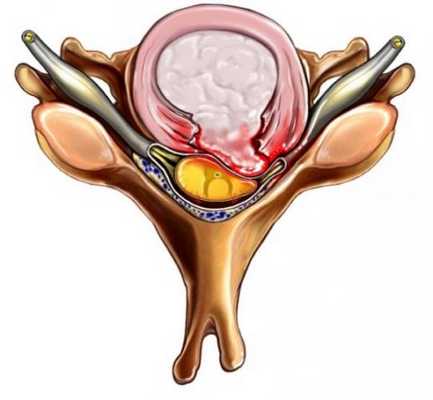

Пример-схема экструзий диска при расшифровке КТ позвоночника. Слева –фораминальная экструзия (грыжа) со сдавлением дурального мешка; посередине – фораминальная экструзия со сдавлением нервного корешка, справа – секвестрированная грыжа диска (секвестр отмечен звездочкой «*»)